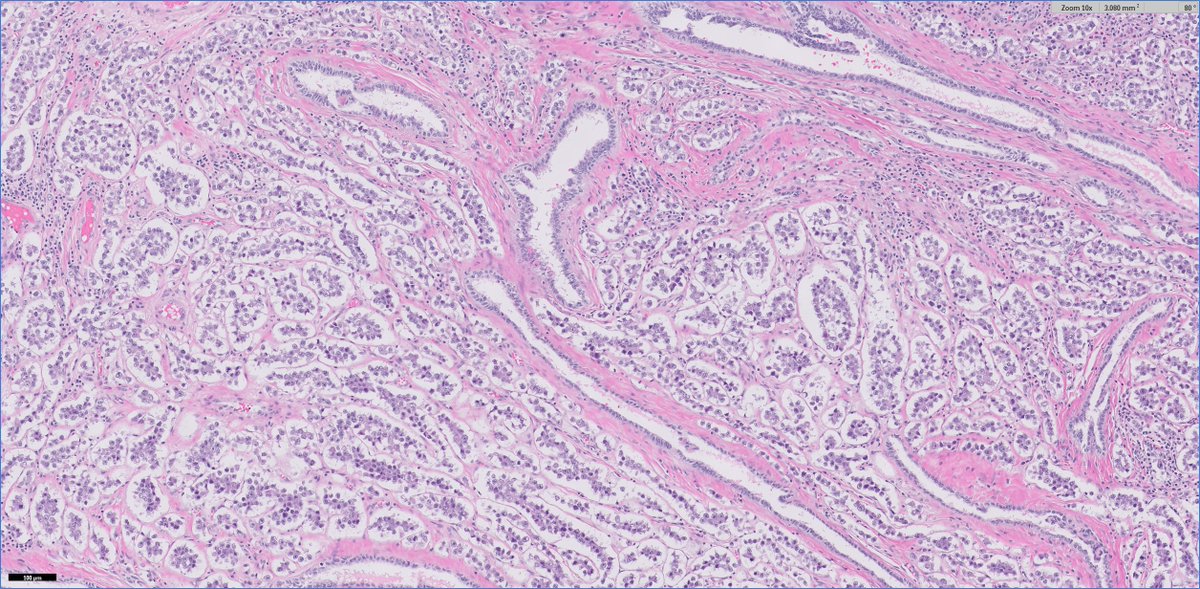

#GUpath🧩 time!

30ish M (no priors) presents with testicular mass and undergoes radical orchiectomy

🔬🤔❓